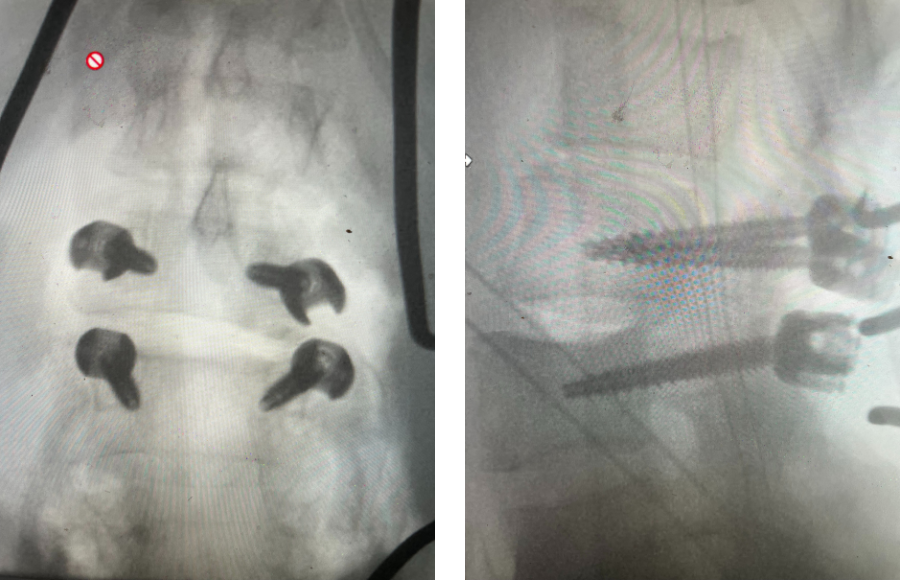

The spinal synovial cyst is one of the most interesting expressions of spinal instability. They emanate from the synovial lining of a degenerated facet joint that […]

People are obsessed with cysts! When you think about it, the body likes to form cysts. Why does this happen? Cysts can form just about anywhere […]